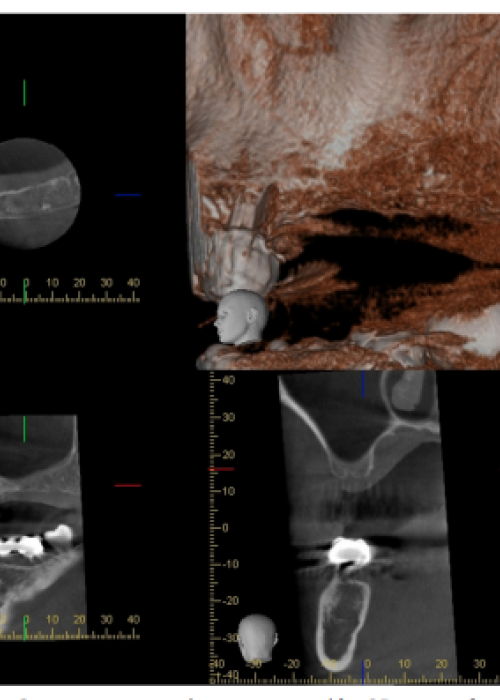

Elevación de seno con Betafosfato Tricálcico y posterior colocación de implantes. A propósito de un caso